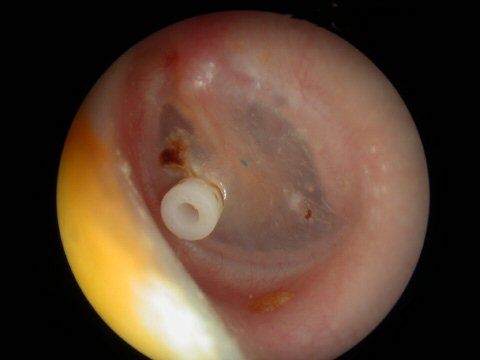

Ear tubes - The first picture shows an ear tube that has fallen out but is stuck to ear canal by ear wax. The last picture shows a T-tube, these stay in place much longer but run the risk of leaving a permanent perforation when finally removed.